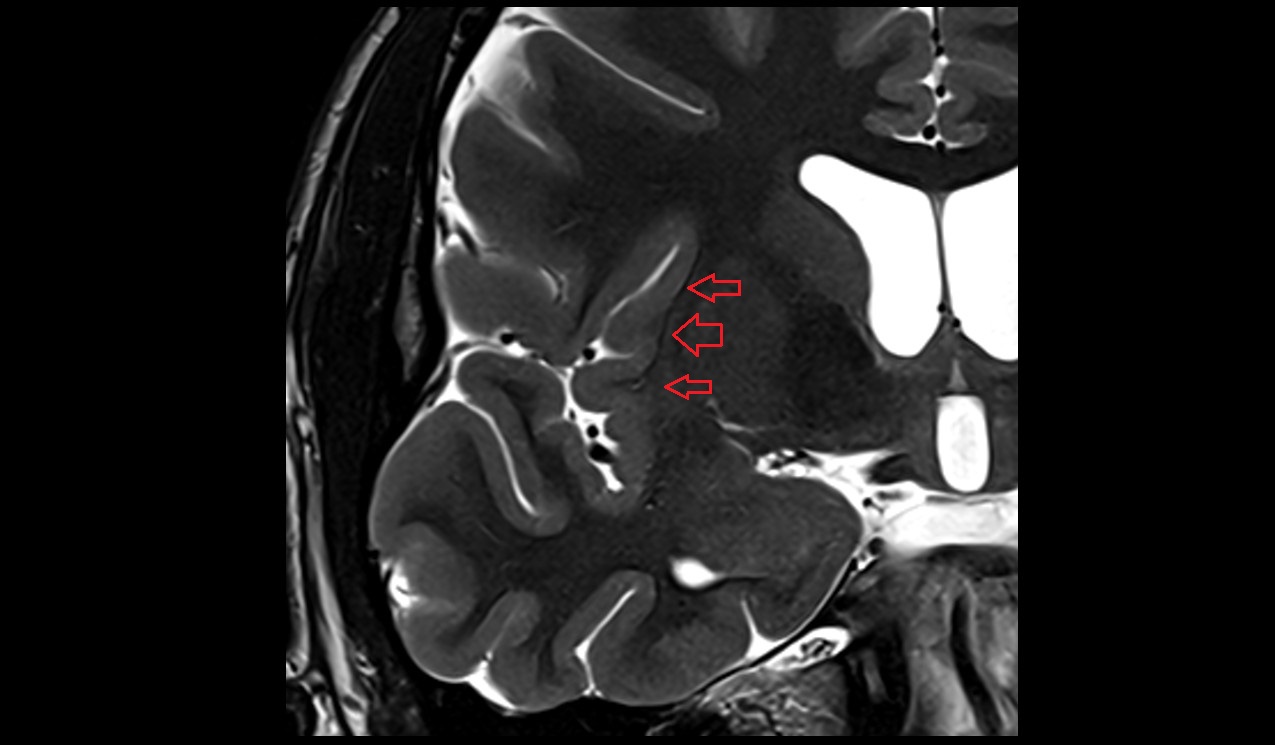

- Body of hippocampus

- Head of hippocampus

- Tail of hippocampus

- Hippocampus